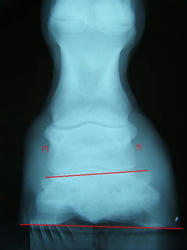

9月の左前肢

ラメラーウェッジがだいぶ取り除かれ、蹄が蹄壁にきちんとくっついて生えてきているのが確認できてホッとしました。